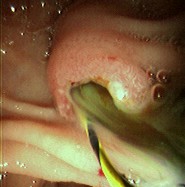

Colangitis aguda

Foto endoscópica del mismo paciente después de la extracción del cálculo de gran tamaño del conducto biliar común (CBC); nótese el copioso pus que se drena a través de la ampolla

De la colección de Douglas G. Adler; usado con autorización